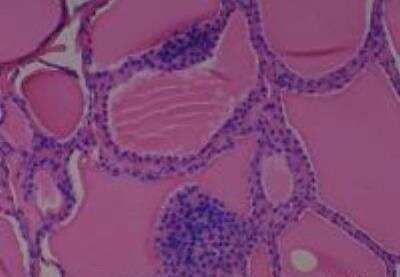

Scientific Data Images for Human Multi Tissue MicroArray (Normal Adjacent)

Hematoxylin & Eosin Stain: Human Common Tissue MicroArray (Normal Adjacent) [NBP2-30215] - 01. Stomach

Hematoxylin & Eosin Stain: Human Common Tissue MicroArray (Normal Adjacent) [NBP2-30215] - 102. Stomach

Hematoxylin & Eosin Stain: Human Common Tissue MicroArray (Normal Adjacent) [NBP2-30215] - 103. Stomach